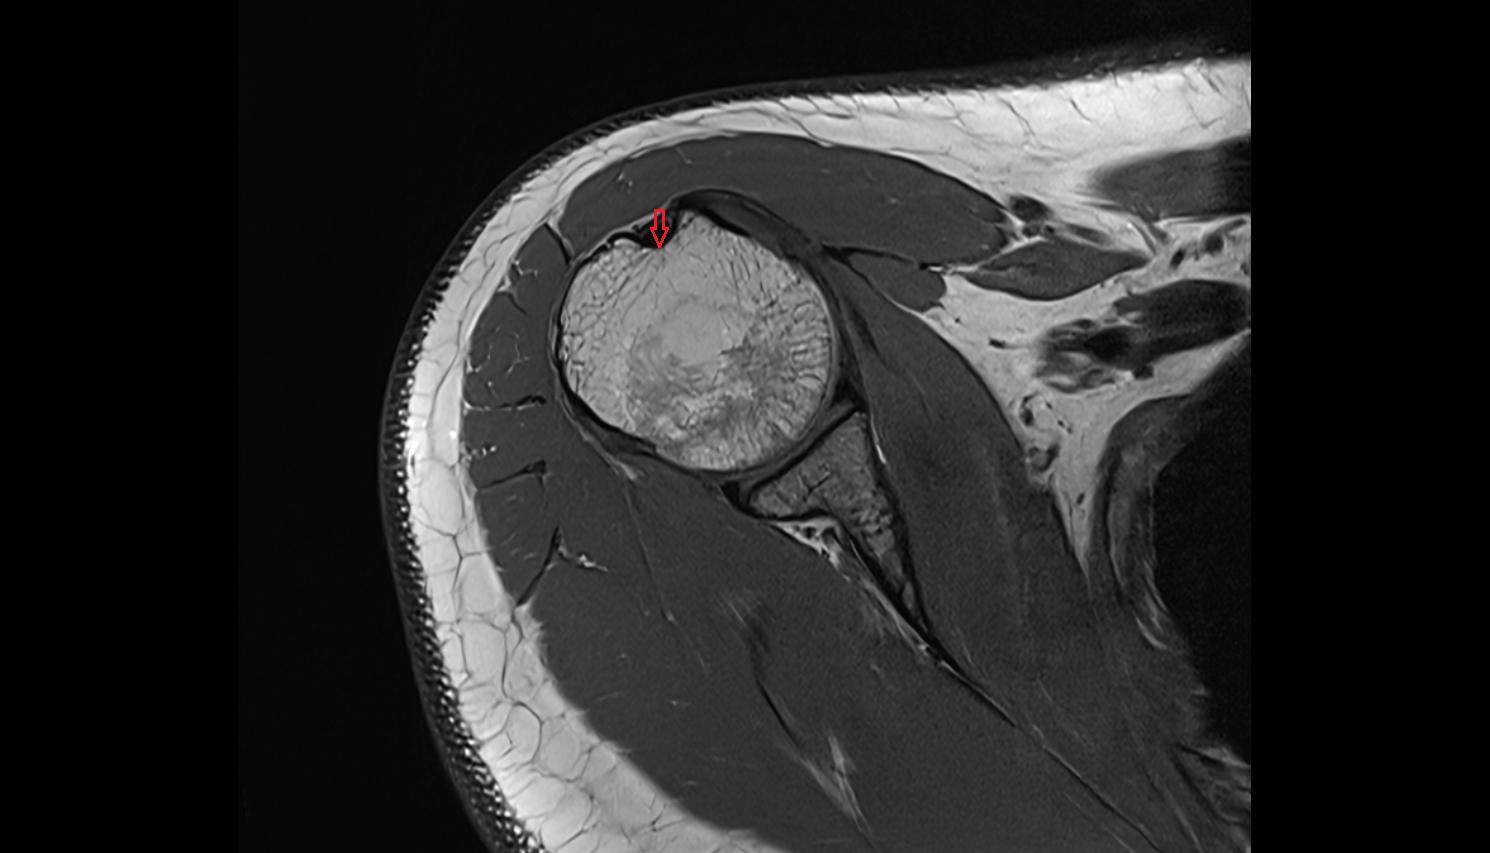

- Shoulder joint (glenohumeral joint)

- Supraspinatus tendon

- Glenoid labrum